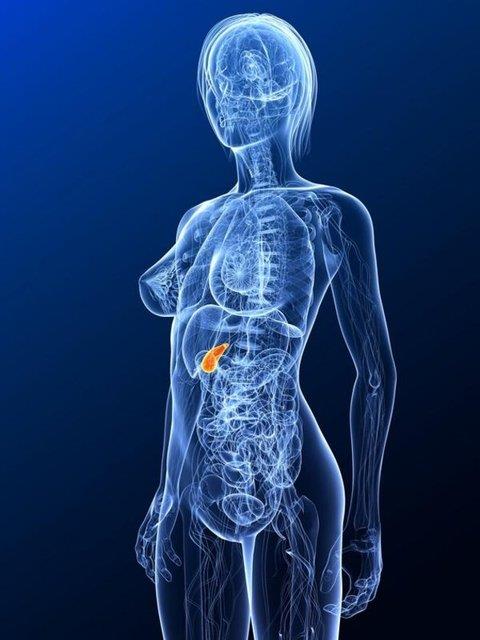

1. Safra kesesi; karaciğerin alt yüzeyinde, ona yapışık, 50 ml hacmi olan, safranın depolanmasını ve konsantre edilmesini sağlayan, armut biçiminde bir organdır.

Safra kesesi; karaciğerin alt yüzeyinde, ona yapışık, 50 ml hacmi olan, safranın depolanmasını ve konsantre edilmesini sağlayan, armut biçiminde bir organdır.